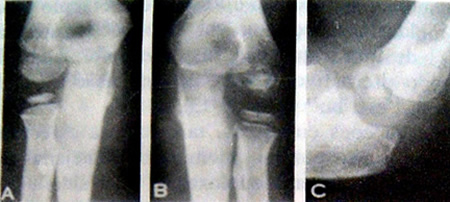

Na doença de Legg-Perthes mais do que em qualquer outra osteocondrose, mesmo com tratamento, o prognóstico é extremamente variável. A idade que se inicia a doença é um fator importante; em geral o prognóstico é bom em crianças cuja doença iniciou-se antes dos cinco anos de idade (Fig. 13-14). Regular em crianças cujo início da doença se deu entre cinco e sete anos de idade (Fig. 13-15) e inato quando se deu acima da idade de sete anos (Fig. 13-16). O prognóstico é definitivamente pior no tipo ‘‘cabeça inteira’’ e na presença de subluxação. Em crianças mais velhas, a falha no Tratamento da doença de Legg-Perthes pode levar a uma deformidade residual grave (Fig. 13-17).

Figura 13-14. Bom prognóstico. A, aos quatro anos de idade perto do fim da fase precoce da recuperação. B, dois anos mais tarde. C, quatro anos mais tarde a cabeça femoral está redonda, um bom resultado.

Figura 13-15. Prognóstico regular. A, aos seis anos de idade, na fase inicial de revascularização. B, um ano mais tarde. C, cinco anos mais tarde a cabeça femoral está grande (coxa magna), porém razoavelmente redonda, um resultado regular.

Figura 13-16. Prognóstico mau. A, aos oito anos de idade, no inicio da fase de revascularização. B. um ano mais tarde existe acentuada subluxação. C, cinco anos mais tarde, a cabeça femoral, além de estar grande, também está achatada (coxa pIana), um mau resultado.